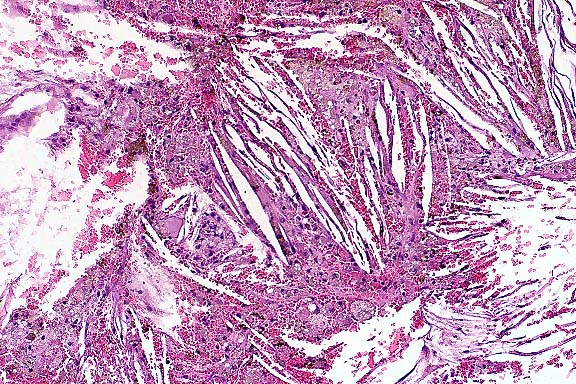

Case 1: Lymph node: Large lymphoid cells with few eosinophilic intracytoplasmic granules fill the subcapsular sinus and paracortical regions and have nearly replaced normal small lymphocytes in the follicular areas. (40x obj).

Jejunal lymph node: High-grade infiltration of the sinuses and the paracortex by medium-sized to large monomorphic, slightly basophilic lymphoid tumor cells. Focal invasion of the capsule and cortical area with partial effacement of the lymph node architecture. Single megakaryocytes can be seen within the sinuses. Within areas of dense tumor cell infiltration there are 3 mitoses per high power filed. The nuclear/cytoplasmic ratio of the neoplastic cells is moderate, numerous nuclei are indented. A marked azurophilic granulation of the cytoplasm near the indentations of the nuclei can be seen in Giemsa-stained plastic sections, whereas this is hardly noticeable in H&E-stained plastic sections and invisible in paraffin section (both H&E- and Giemsa-stained.). The granules react positively for Chloroacetate- esterase and acid phosphatase (plastic sections). The neoplastic cells are labeled by an antibody specific for the epsilon chain of the human CD3 complex (paraffin sections). Tumor cell infiltrations were seen within the tunica muscularis of the jejunum, in the propria mucosae of the gastric fundus, in the lung, in the myocardium, in the kidneys, in the epidural space, in the pachymeninx and in the white substance of the spinal cord.